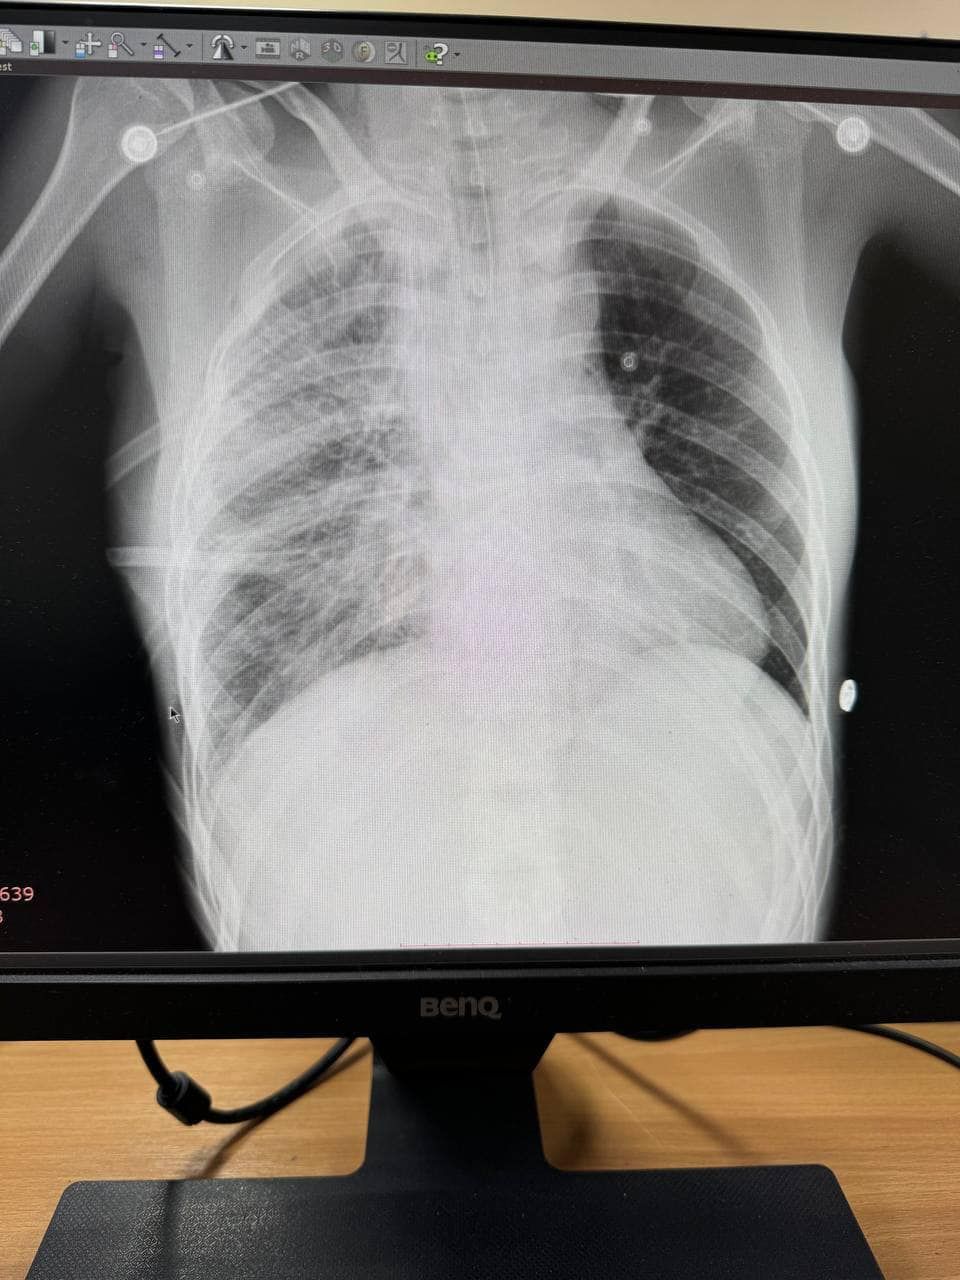

Медики госпитализировали пациента с вблизи проблем, в частности, тяжелым воспалением шеи, разрывом пищевода, воспалительным процессом в клетчатке средостения (участок в грудной полости), гнойным воспалением плевры, инородными телами и опущением желудка.

«Врачами выделения одномоментно выполнено цервикотомию с левой стороны, правостороннюю торакотомию с медиастинотомией, верхне-срединную лапаротомию, гастротомию с наложением гастростомы», – рассказали в отделении больницы.